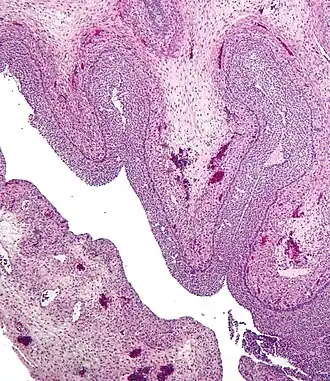

Section of the ovary. 1. Outer covering. 1’. Attached border. 2. Central stroma. 3. Peripheral stroma. 4. Bloodvessels. 5. Vesicular follicles in their earliest stage. 6, 7, 8. More advanced follicles. 9. An almost mature follicle. 9’. Follicle from which the ovum has escaped. 10. Corpus luteum.